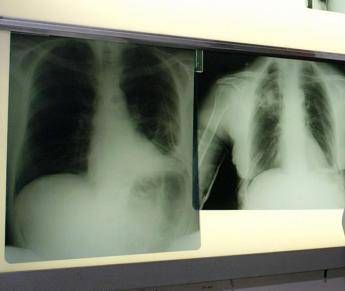

Il virus respiratorio sinciziale colpisce in modo diverso nelle differenti fasce d'età. L'Rsv "è un virus ubiquitario che colpisce praticamente tutti i bambini entro i 2 anni di vita, con possibili reinfezioni nel corso della prima infanzia e financo in età adulta - illustra Paolo Manzoni, professore associato di Pediatria e neonatologia, università di Torino – Se nei soggetti oltre i 2 anni di età il virus causa spesso sintomi simil-influenzali, colpendo per lo più le vie aeree superiori, al contrario una percentuale importante di pazienti con età meno di 2 anni presenta coinvolgimento delle basse vie aeree che può sfociare, nello specifico, nel quadro clinico classico conosciuto come bronchiolite e nelle sue complicanze sia immediate, sia a lungo termine". Oltre ai neonati prematuri e di età inferiore ai 6 mesi, le popolazioni a rischio di sviluppare una patologia respiratoria grave a seguito di Rsv sono le persone over 60 e quelle immunocompromesse o con patologie preesistenti come il diabete, le malattie cardiache e polmonari, nelle quali il virus può scendere alle vie respiratorie inferiori causando principalmente polmonite.